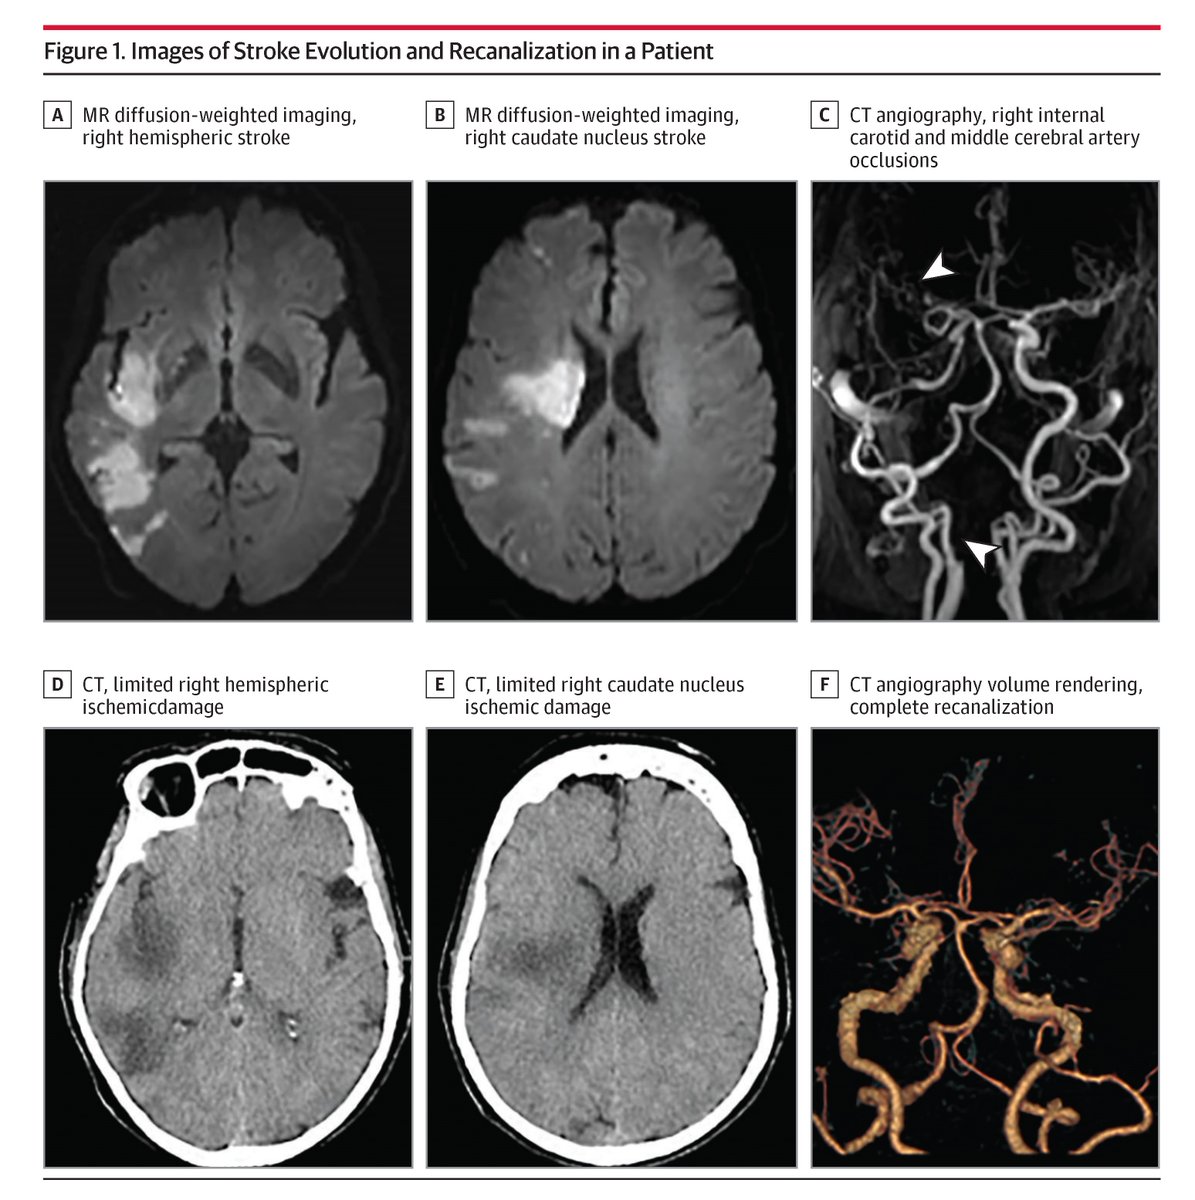

#STROKE November Cover Figure: Is it time to rethink the ischemic core in MRI? Acute ischemic DWI lesions with high OEF may recover after successful thrombectomy. #DWI #OEF #Perfusion #Thrombectomy #Neuroimaging #AHAJournals ahajrnls.org/3Z3eFzo